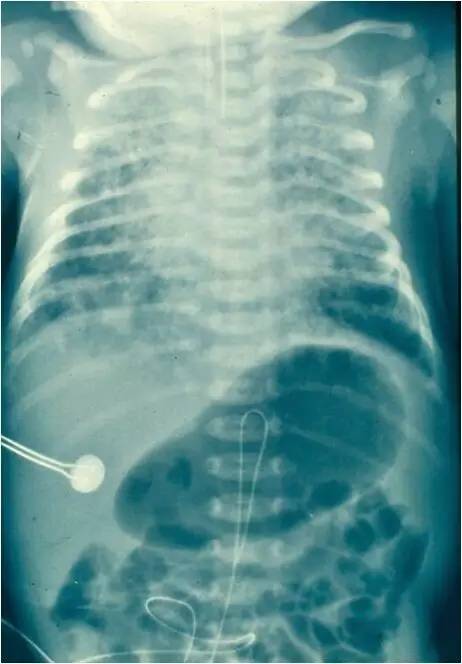

MAS影像学表现

临床特征